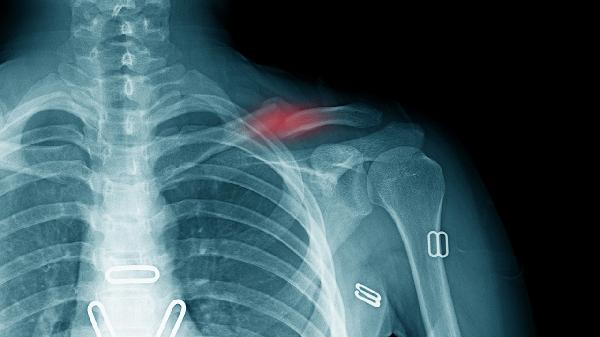

锁骨骨折多数情况下无需手术治疗。治疗方案选择主要取决于骨折类型、移位程度、患者年龄等因素,保守治疗方式包括八字绷带固定、锁骨带固定、限制活动、物理治疗及药物镇痛。

无移位或轻度移位的锁骨中段骨折通常选择保守治疗。这类骨折稳定性较好,通过外固定可达到自然愈合,愈合周期约6-8周。若为粉碎性骨折或伴有血管神经损伤,则需手术干预。

骨折端重叠小于2厘米或成角小于30度时优先考虑非手术治疗。严重移位可能导致畸形愈合影响肩关节功能,此时需手术复位内固定。儿童锁骨骨折因骨膜较厚,即使明显移位也多可保守治疗。